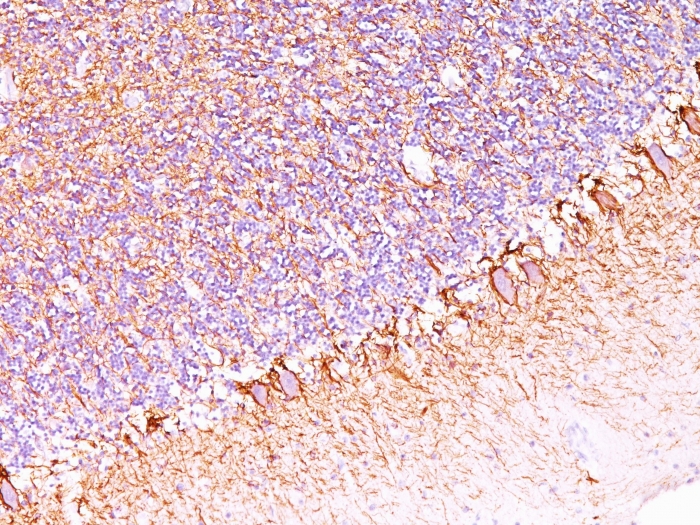

This MAb reacts with a 200kDa protein, identified as heavy sub-unit of neurofilaments (NF-H). Neurofilaments make up the main structural elements of axons and dendrites and are found in neurons, peripheral nerves, and sympathetic ganglion cells. Neurofilaments consist of three major subunits with molecular weights of 68kDa (NF-L), 160kDa (NF-M) and 200kDa (NF-H). Anti-neurofilament stains a number of neural, neuroendocrine, and endocrine tumors. Neuromas, ganglioneuromas, gangliogliomas, ganglioneuroblastomas, and neuroblastomas stain positively for anti-neurofilament. Neurofilaments are also present in paragangliomas as well as adrenal and extra-adrenal pheochromocytomas. Carcinoids, neuroendocrine carcinomas of the skin, and oat cell carcinomas of the lung also express neurofilament.

Brain, Neuroblastoma.